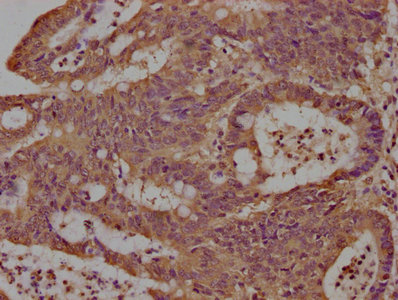

IHC image of CSB-PA012231LA01HU diluted at 1:100 and staining in paraffin-embedded human colon cancer performed on a Leica BondTM system. After dewaxing and hydration, antigen retrieval was mediated by high pressure in a citrate buffer (pH 6.0). Section was blocked with 10% normal goat serum 30min at RT. Then primary antibody (1% BSA) was incubated at 4°C overnight. The primary is detected by a biotinylated secondary antibody and visualized using an HRP conjugated SP system.